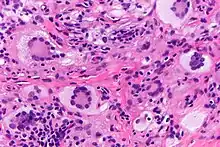

Touton giant cells, being multinucleated giant cells, can be distinguished by the presence of several nuclei in a distinct pattern. They contain a ring of nuclei surrounding a central homogeneous cytoplasm, while foamy cytoplasm surrounds the nuclei.[4][5] The cytoplasm surrounded by the nuclei has been described as both amphophilic and eosinophilic, while the cytoplasm near the periphery of the cell is pale and foamy in appearance.[6]